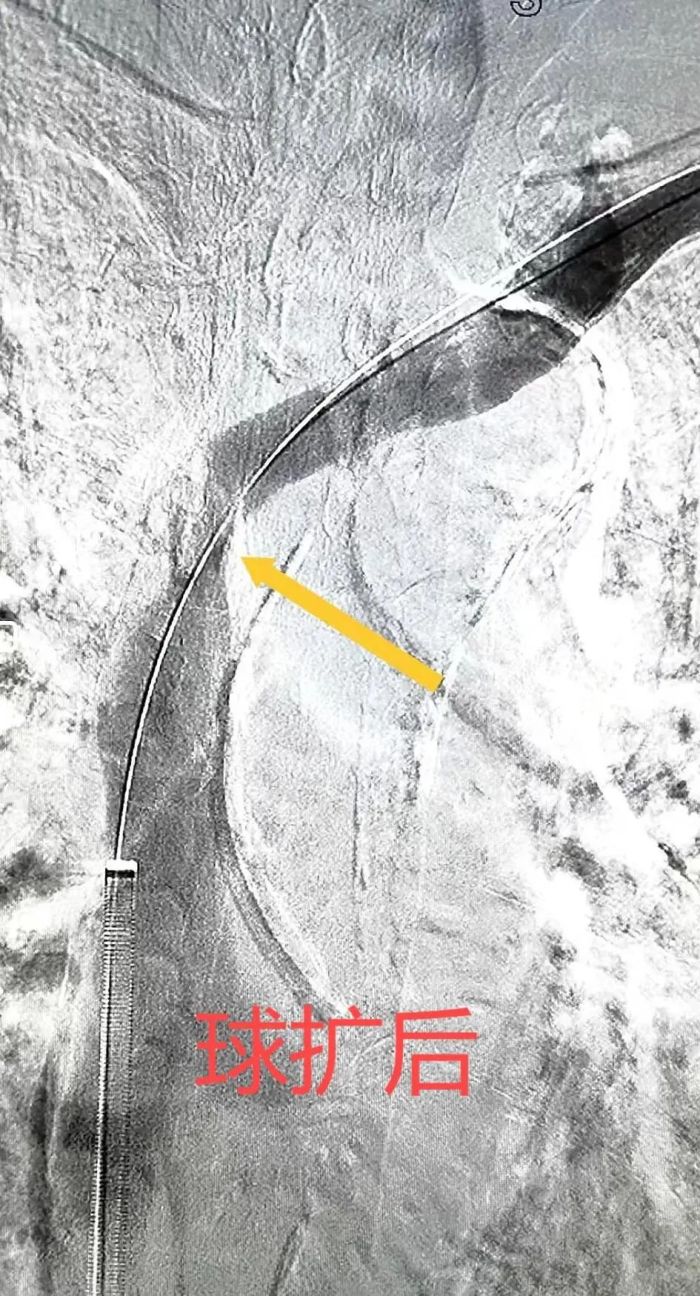

术中,李全明教授对病变血管进行了球囊扩张、支架植入与开通血管,在一小时内顺利解决了患者左头臂静脉开口段狭窄的问题。术后,患者的头面部水肿迅速消退,透析通路的通畅程度也得到了显著改善,生活质量有了明显提升。患者和家属对手术效果非常满意,对血管外科团队表示了衷心的感谢。

随着血管腔内微创技术和器械的发展,广大透析患者常面临的透析通路后期各种维护和并发症的难题,都可以通过微创腔内手术进行治疗。目前,除了传统的药物治疗外,血管腔内介入技术如球囊扩张和支架植入术已成为重要的治疗手段。中南大学湘雅二医院桂林医院血管外科团队将继续做好“生命线”的养护工作,为广大透析患者提供更多的选择和希望。